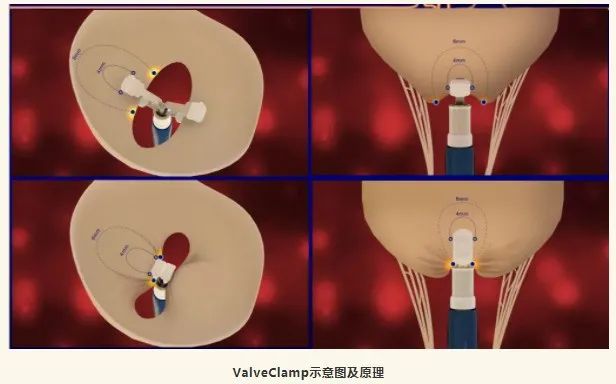

近日,复旦大学附属中山医院心研所团队使用该团队和上海捍宇医疗科技有限股份公司(简称捍宇医疗)合作研发的世界首款经心尖二尖瓣夹合器ValveClamp,完成10例功能性二尖瓣反流(FMR)患者进行探索性研究,取得满意的结果。该研究由葛均波院士、王春生主任、周达新教授、魏来教授及潘翠珍教授等完成。

ValveClamp为世界首个经心尖二尖瓣夹合器,目前已获得全球多个国家PCT专利授权。该器械相对于目前国际上其他的经导管缘对缘修复(TEER)器械,具有一些独特优势: